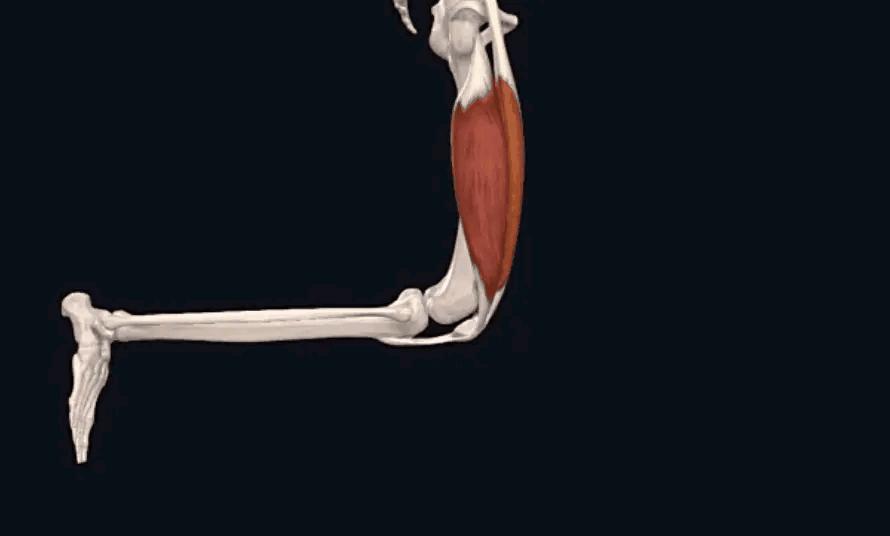

想想看,每天久坐的时候,与凳子接触最多的是臀部,臀部上有很多肌肉。如下图所示:

若每天让这些臀部肌肉压在凳子上长达几个小时,是种什么感觉呢?答案就是像我们跪在哪一会起身时那种酸麻胀痛不适的感觉,长此以往,这些臀部肌肉是不可能禁得起压迫的,势必会出现问题。

同时在久坐后,骨盆关节的灵活性降低,直接会对髋关节的短外旋肌群有影响,特别是臀部的梨状肌,压迫受损后,触发点也会激活,产生臀部的不适,甚至压迫下方走行的神经。

所以,当您久坐之后,不仅会影响骨盆,还会影响骨盆上的臀肌,出现无力、缺血,卡压坐骨神经、臀上皮神经等,导致下肢疼痛、行走时无力、走不远。